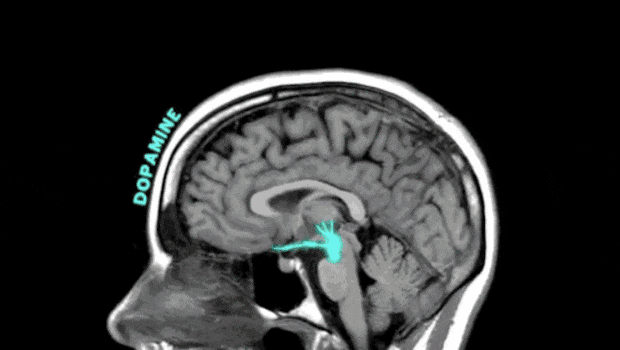

多巴胺

它是大腦獎勵系統的重要部分,與愉悦感覺有關,還參與到人體日常的學習、記憶、運動系統功能之中。